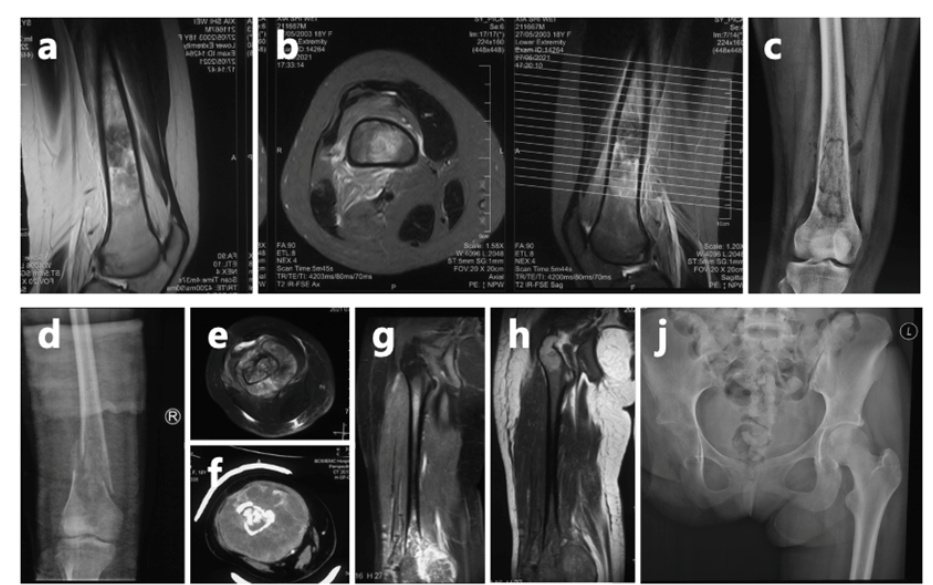

18岁确诊骨癌,19岁截肢,23岁面临多处转移, 这就是夏夏过去五年的青春。肺叶切除,六次大手术,无数次化疗。为了“活下去”这个简单的愿望,她付出了常人难以想象的代价。

上海市第一人民医院骨肿瘤科曾讲述过夏夏的经历:她确诊骨肉瘤后经历了6次手术和无数次挑战,自2023年8月接诊以来,又完成了10次化疗和2次手术。医护人员回忆,第一次见到夏夏,她戴着假肢,拄着拐杖,拉着一个与她身高差不多的行李箱,独自走进医院。这一幕让人既心疼又敬佩。

市一骨肿瘤科介绍,对于夏夏来说,此前的截肢是一个相对可靠的选择。由于肿瘤已推挤下肢的血管和神经,并累及髋关节,截肢手术能够降低肿瘤复发的几率。然而,截肢会导致术后肢体功能的永久性丧失,对患者心理和生活质量可能造成一定影响。尽管困难重重,她始终以微笑和坚韧面对一切。

夏夏前期接受了术前化疗、截肢手术及术后化疗,使用的是一线化疗方案。然而,结疗不到一年,肺部出现转移病灶,这种情况是恶性肿瘤的普遍特性,骨肉瘤患者中并不少见,尤其是结疗后2年内,是转移和复发的高发期。

为帮助她巩固疗效并延长无病生存期,2024年2月,夏夏经过手术切除后未再进行化疗。术后5个月,左肺再次发现新发转移病灶。2024年11月,夏夏接受胸腔镜下右肺下叶切除术。2025年1月复查:右肺术后改变好转。